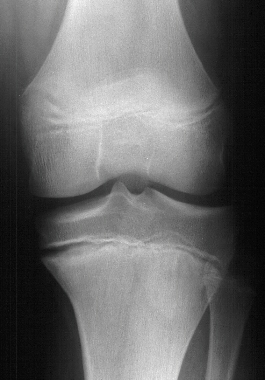

Lateral

epiphysiodesis of the tibia is a good treatment.